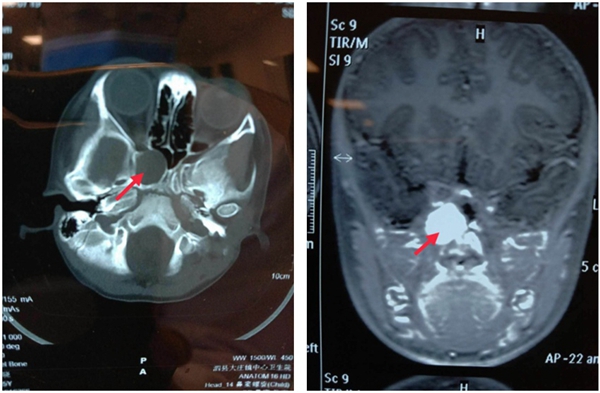

患者是一名5歲的女孩,在外院做MRI診斷右側(cè)眶尖中顱底占位(2.1×2×2cm),考慮病情復(fù)雜、手術(shù)風(fēng)險(xiǎn)大,輾轉(zhuǎn)幾家醫(yī)院求助無(wú)果后,入住蚌醫(yī)一附院耳鼻咽喉頭頸外科三病區(qū)。主任醫(yī)師王文忠接診后,考慮患者年齡較小,腫瘤位于眶尖與蝶骨翼內(nèi)板的狹窄骨性空間內(nèi),該區(qū)域分布著視神經(jīng)、頸動(dòng)脈等重要結(jié)構(gòu),稍有偏差將導(dǎo)致失明、致命性大出血等嚴(yán)重的并發(fā)癥。王文忠主任與副主任醫(yī)師周蘭柱、主治醫(yī)生孫哲、吳俊等組成治療組,認(rèn)真分析術(shù)中可能出現(xiàn)的風(fēng)險(xiǎn),制定了詳細(xì)周密的手術(shù)方案,決定在導(dǎo)航引導(dǎo)內(nèi)鏡下行腫瘤切除術(shù)。

2020年10月16日上午,手術(shù)室付芹、李莉護(hù)士長(zhǎng)仔細(xì)調(diào)試好手術(shù)設(shè)備,在李曉紅主任,王濤濤麻醉師的精心監(jiān)護(hù)下手術(shù)開(kāi)始了,術(shù)中導(dǎo)航下手術(shù)醫(yī)生小心翼翼地剝離著腫瘤,精準(zhǔn)避開(kāi)視神經(jīng)、頸動(dòng)脈等重要神經(jīng)和血管結(jié)構(gòu),保證每一個(gè)細(xì)微的動(dòng)作不能有絲毫偏差……歷時(shí)兩個(gè)小時(shí),成功切除腫瘤,解除了因腫瘤進(jìn)一步發(fā)展而壓迫視神經(jīng)導(dǎo)致患者失明的危害。術(shù)后病理報(bào)告為“鼻顱底梭形細(xì)胞瘤,傾向于神經(jīng)纖維瘤”。在張培培護(hù)士長(zhǎng)帶領(lǐng)的護(hù)理團(tuán)隊(duì)精心護(hù)理下,一周后患者順利康復(fù)出院,無(wú)任何并發(fā)癥發(fā)生。此次手術(shù)在省內(nèi)該領(lǐng)域處于領(lǐng)先水平。